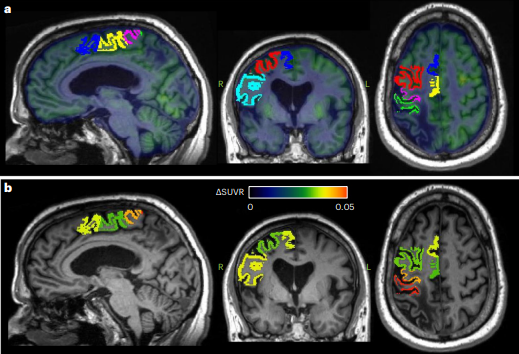

La investigación de Baker et al. (2023) se enfocó en una novedosa aproximación: la estimulación continua del núcleo dentado cerebeloso para modular la actividad neural y la excitabilidad cortical ipsilesional.

Esta hipótesis se basó en investigaciones electrofisiológicas de la vía cerebelo-talámo-cortical. En esa misma línea, se sostiene que la reorganización cortical y formación de sinapsis destacan por su relevancia en la recuperación de la motricidad. Respecto a dicha hipótesis, se aplicó en un grupo de 12 sobrevivientes de ACV, con discapacidad moderada a severa en el miembro superior.